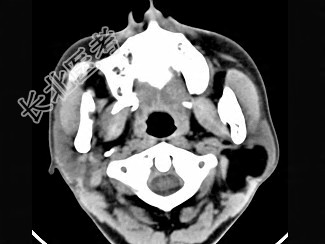

- 单项选择题女性50岁,左侧面部肿胀, CT检查如图,应考虑为 ( )

A、左侧腮腺囊腺瘤

B、左侧腮腺囊肿

C、左侧腮腺脂肪瘤

D、左侧腮腺错构瘤

E、左侧腮腺炎